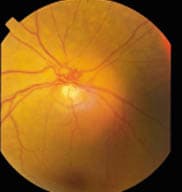

Optic disk photographs showing large c/d ratios

OS.

After dilation, I examined Sadie's optic nerves with a 78.00D lens. They looked classically glaucomatous. Sadie was a +4.00D hyperope and she had small optic nerve heads (ONH), yet her cup-to-disc ratio (c/d) was large and asymmetrical. I estimated her c/d ratio at .55 OD and .7/.7 OS (see photo at left). In addition, the cupping was deep and the lamina was visible in the base of the cup.

Optic disk photographs showing large c/d ratios OD. |